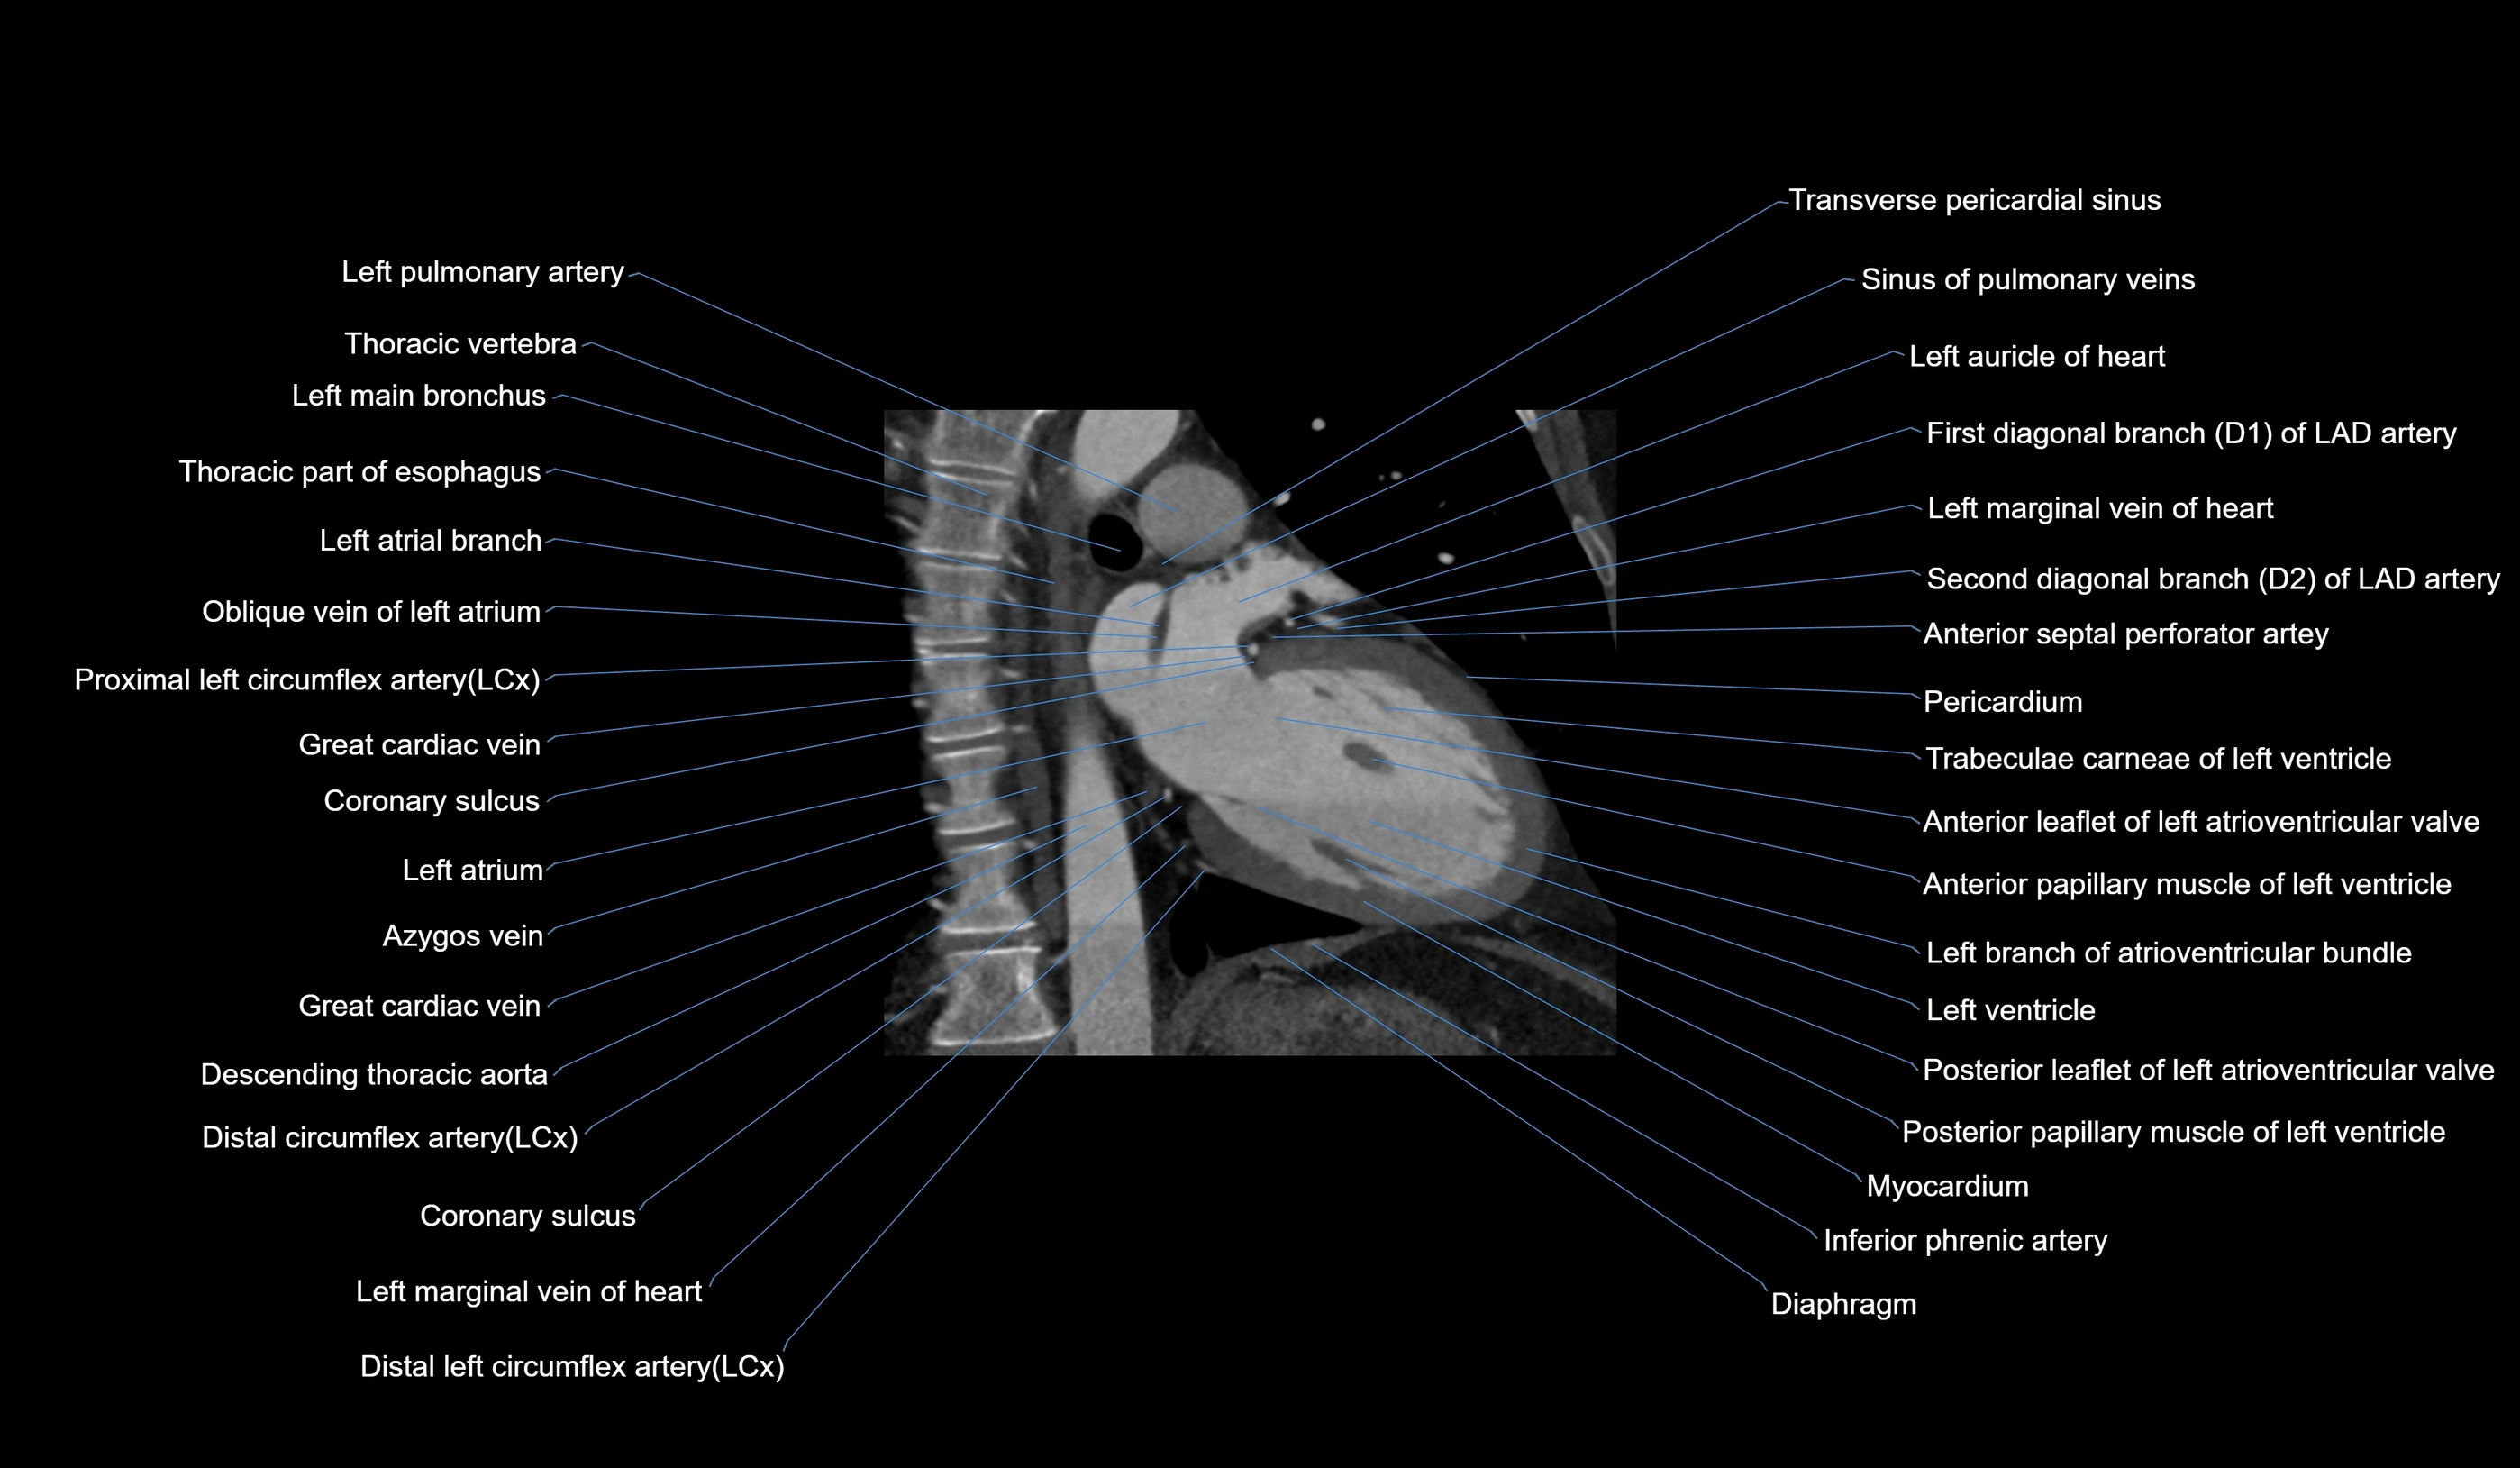

CT images